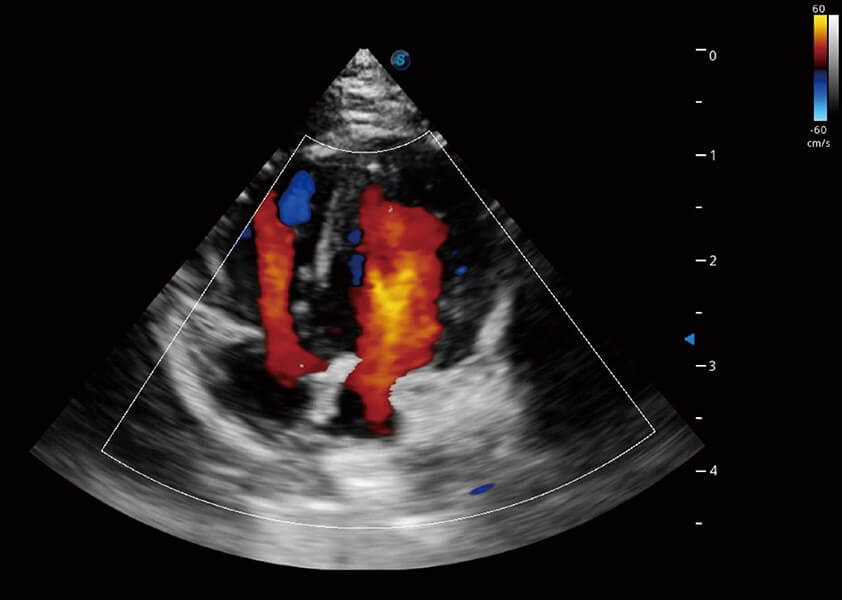

ProPet 60 作為一款高端臺式動物超聲設(shè)備,為動物醫(yī)生的日常診斷提供了一系列貼合動物臨床需求、解決臨床實(shí)際問題的高級成像功能。憑借全系列高清探頭,滿足醫(yī)生對腹部、心臟、生殖、淺表、肌骨等成像的所有需求,切實(shí)幫助您提升檢查效率,提高診斷信心。